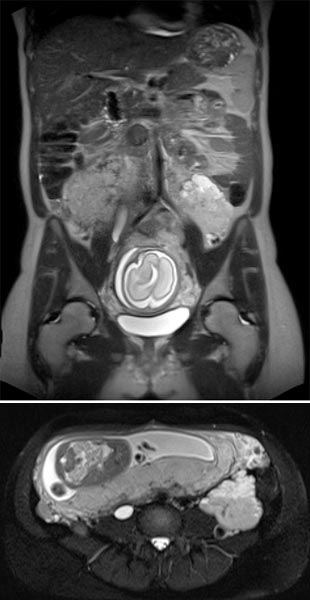

Coronal (top) and axial (bottom) T2-weighted sequences without contrast at 21 weeks' gestation.

Marked increase in size of the VM during pregnancy, which is visualized ventrally of the left psoas muscle as a signal-intense lesion, without displacement or compression of the placenta.

Coronal T2 sequences depicting progression of the VM ventrally sitting on the left psoas muscle at 21 weeks’ gestation. During pregnancy, the patient also develops grade 3 right-sided hydronephrosis.

In the axial T2-HASTE sequence at 21 weeks' gestation, the VM is adjacent to the placenta without displacement of the uterus or fetus.